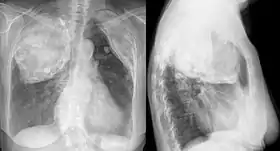

![]() X-ray in an elderly woman after pneumonolysis | |

Pneumonolysis, sometimes referred to as plombage, is the separation of an adherent lung from the pleura, to permit collapse of the lung. It was formerly used to treat tuberculosis before effective medications were developed.[1]

The technique involved surgically creating a cavity underneath the ribs in the upper part of the chest wall and filling this space with some inert material. A variety of substances were typically used and included air, olive or mineral oil, gauze, paraffin wax, rubber sheeting or bags and Lucite balls. The inserted material would force the upper lobe of the lung to collapse.